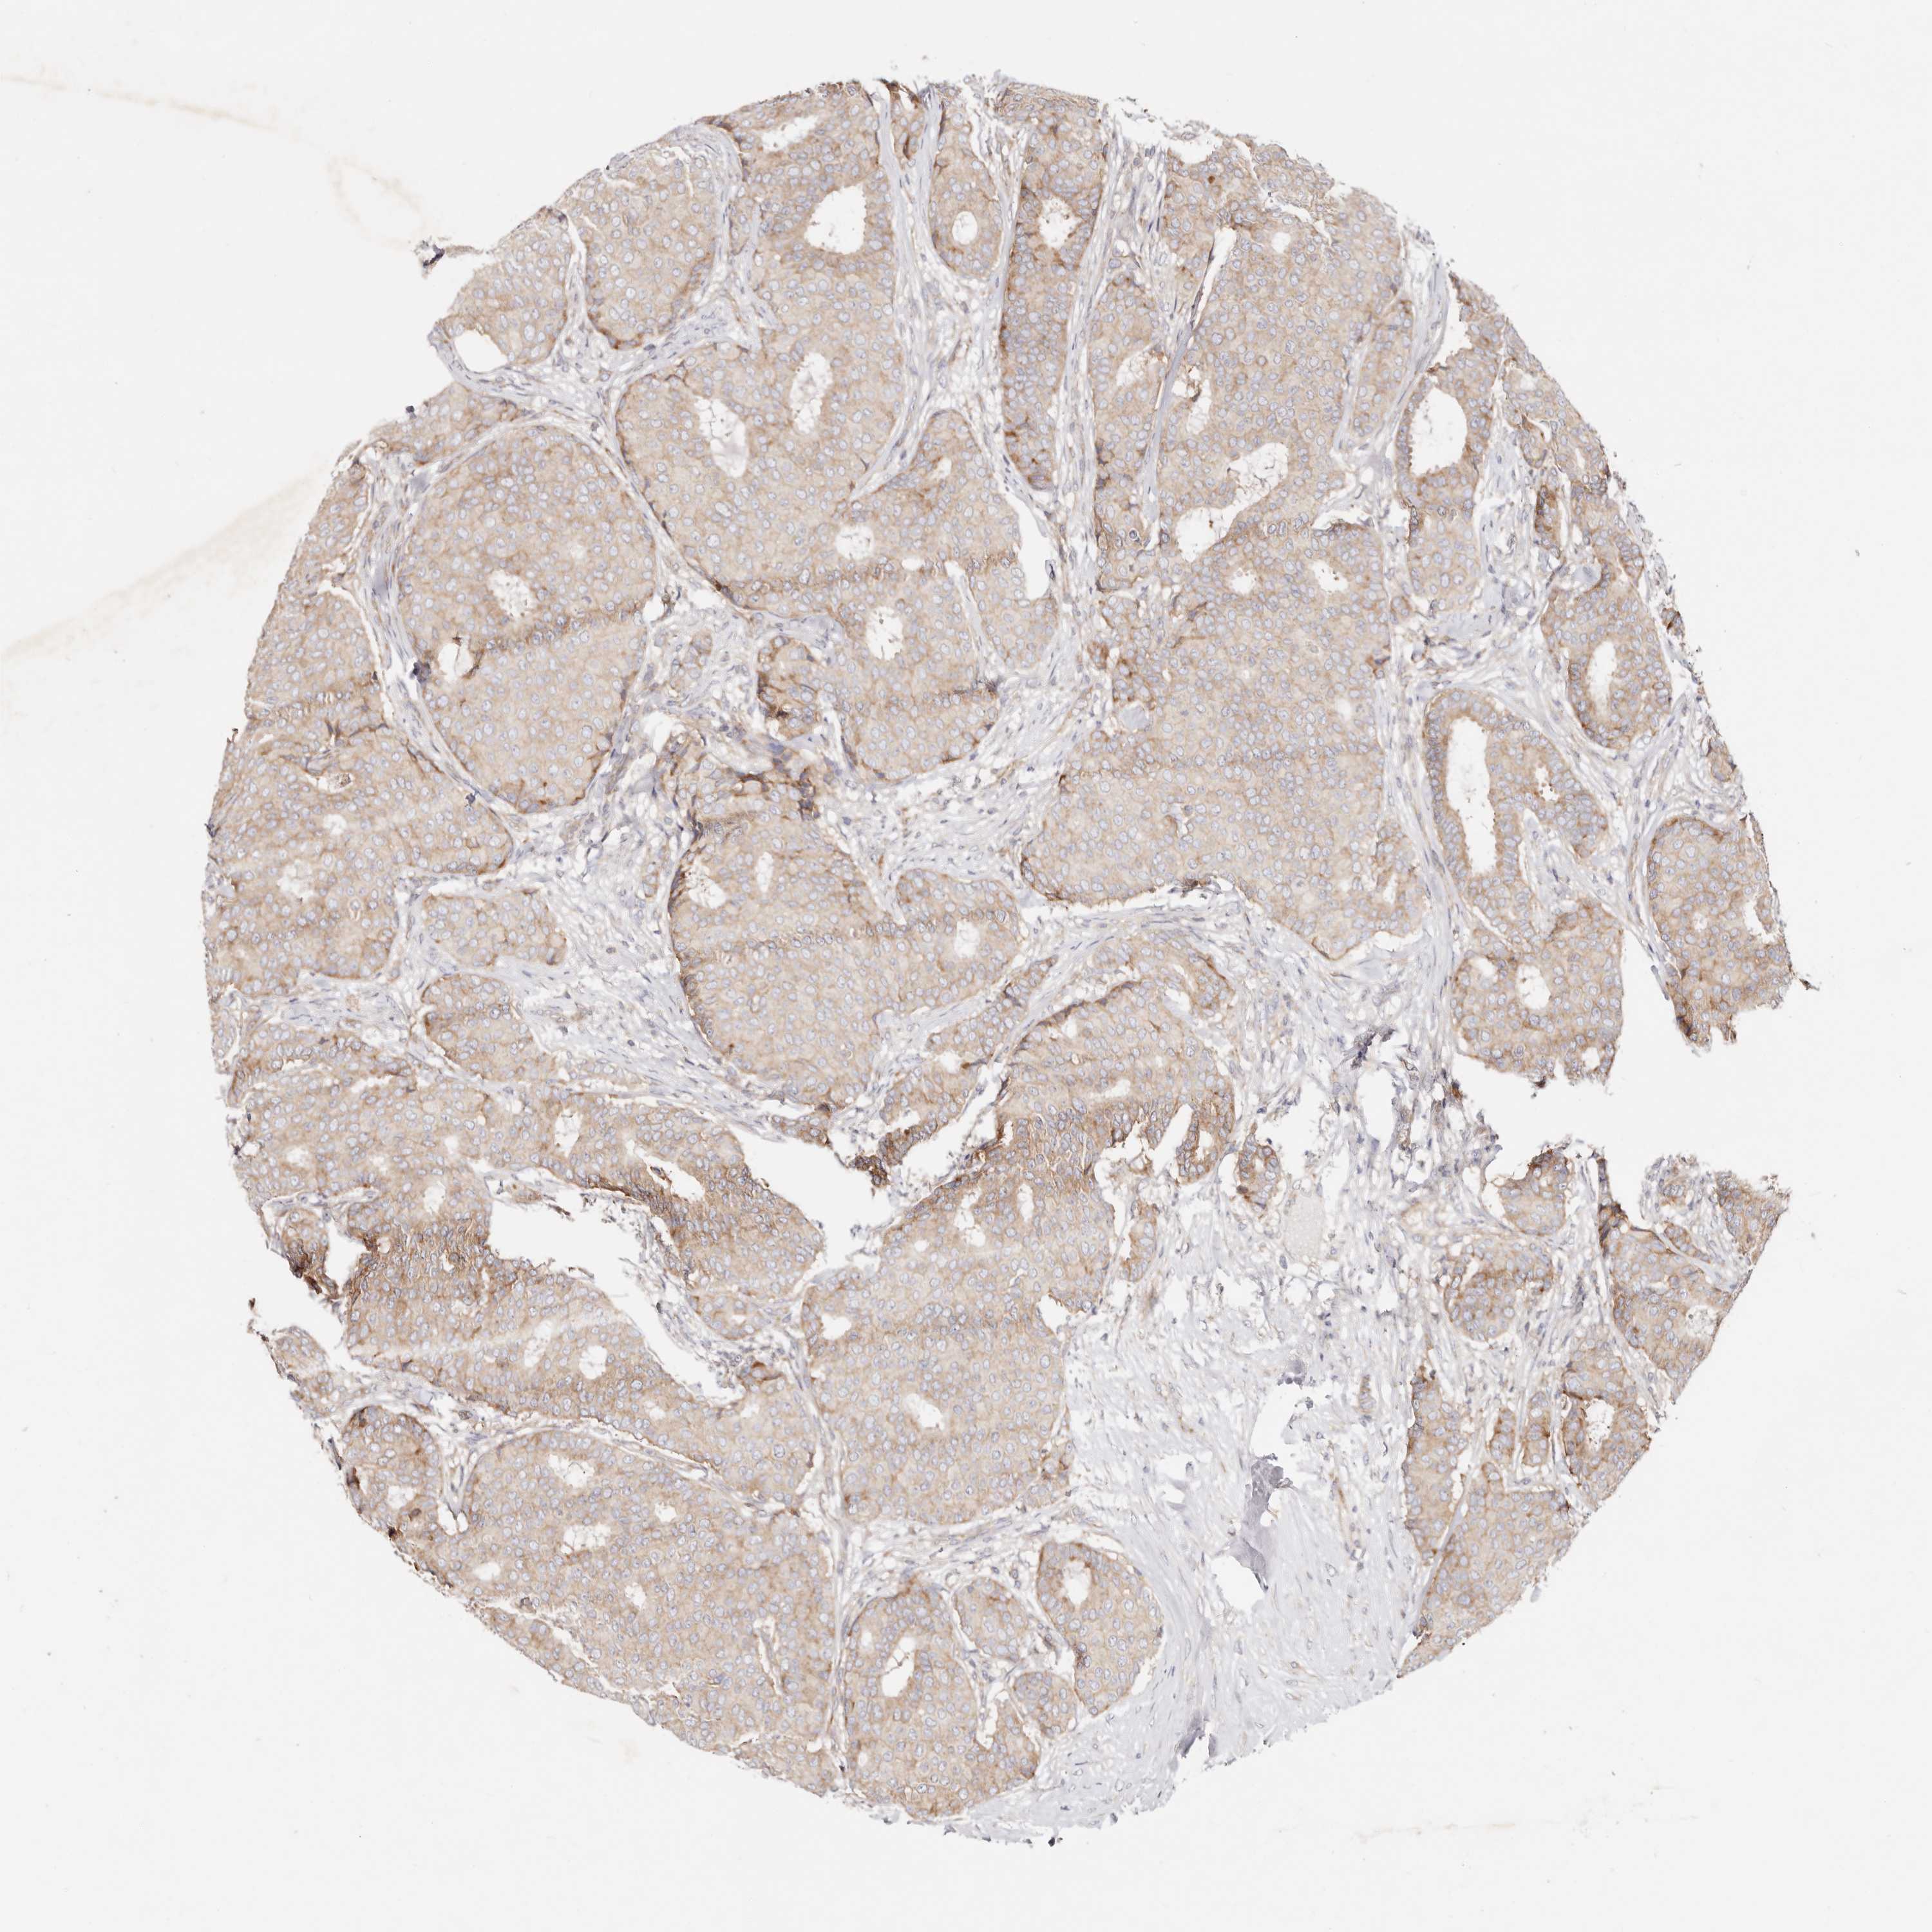

CANCER BREAST CANCER Show tissue menu

BRCA TCGA BRCA VALIDATION PROTEIN EXPRESSION